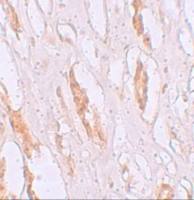

WB analysis of human stomach tissue lysate using GTX31778 ALDH3A1 antibody.

Working concentration : (A) 1 and (B) 2 μg/ml